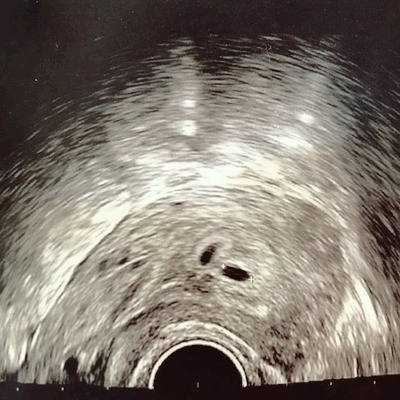

처음 본 초음파 검사 화면에는 좁쌀만 한 물방울 두 개가 찍혀 있었다. “쌍둥이네요.” 의사는 연신 축하 인사를 건넸다. 다름 아닌 바로 내가, 임신을 했다는데 쌍둥이라는데! 정작 나는 잘 모르겠다. TV 다큐 프로나 유튜브 영상 접한 것 마냥. 마치 나와는 관련 없는 일을 지켜보고 있는 것 같았다.

병원에서 처음 본 초음파 화면에는 6mm 크기 '물방울 두 개'가 선명하게 찍혀있었다.